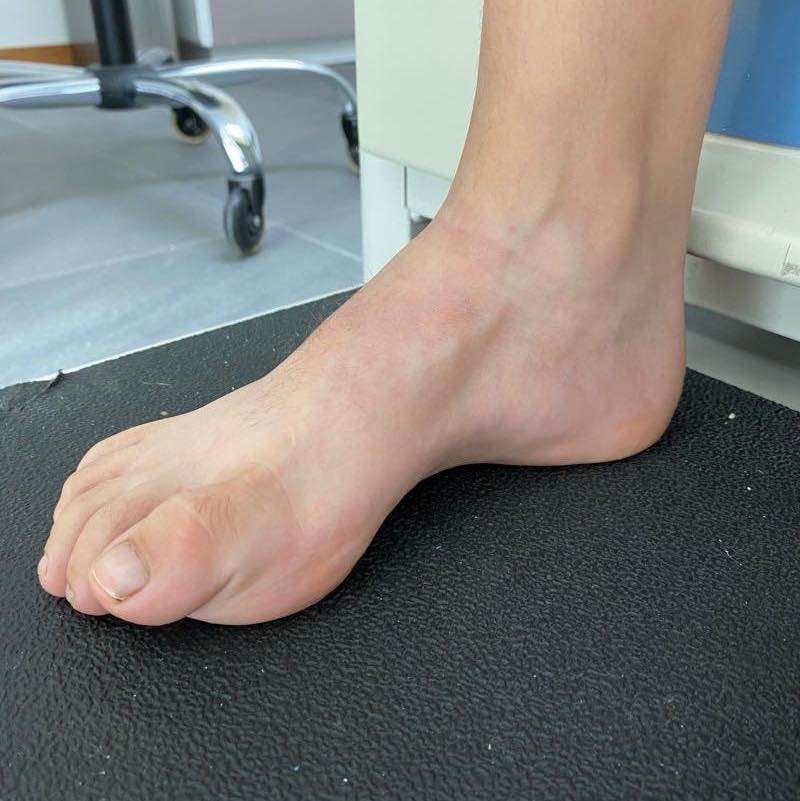

• Pie plano patológico del adolescente

Pie plano infantil

El tratamiento debe ser enfocado solo a aquellos pies que sean dolorosos y que presenten una deformidad importante que impida el uso de calzado habitual. El mejor tratamiento es la rehabilitación y para aquellos que sean rígidos será necesario estudiarlos para descartar la coalición tarsal o alguna otra enfermedad.